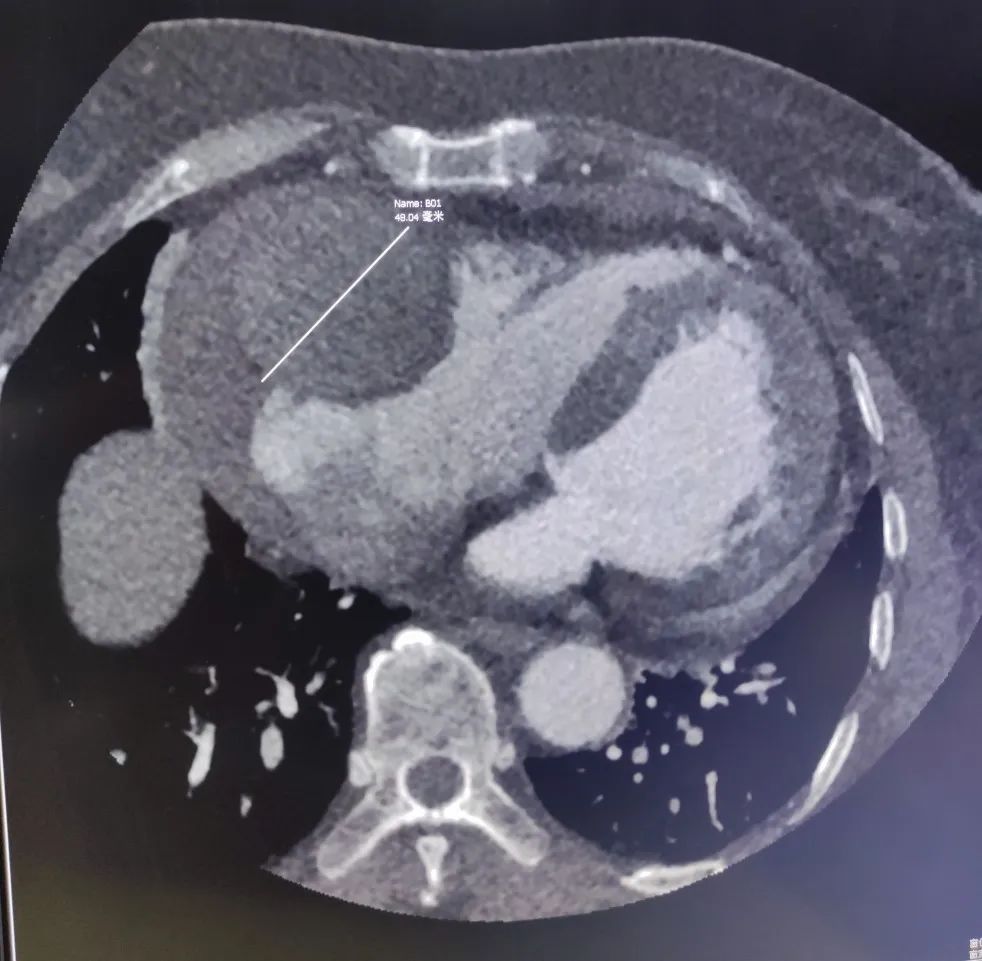

冠状动脉瘤的形成原因在于,各种因素影响下动脉中膜层弹力板断裂破坏,动脉内压力作用下管壁逐渐膨胀,形成瘤样扩张结构。

巨大动脉瘤原因排除冠脉粥样硬化。